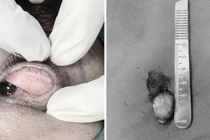

​Tại bệnh viện, sau khi thăm khám và làm các cận lâm sàng cần thiết, các bác sĩ xác định bệnh nhân bị u nang ống Muller bẩm sinh – một dạng dị tật hiếm gặp, dễ nhầm lẫn với các bệnh lý phụ khoa khác. Khối u có kích thước khoảng 8x7cm, nằm sâu trong vùng chậu.

Bệnh nhân được chỉ định phẫu thuật nội soi ổ bụng. Ê-kíp phẫu thuật đẩy bàng quang xuống thấp, bộc lộ khối u nang nằm giữa khoang bàng quang – âm đạo.

Phẫu thuật nội soi giúp bảo tồn các cơ quan, hạn chế xâm lấn và rút ngắn thời gian hồi phục. Sau mổ, các triệu chứng như đau, tiểu đau tiểu khó biến mất hoàn toàn, không còn dấu hiệu sa âm đạo nữa.